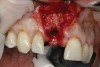

A 56-year-old female patient was referred for the evaluation of tooth No. 8 (Figure 4 and Figure 5). A periapical radiograph indicated that the tooth had undergone apicoectomy and received an excessively long post (Figure 6), and a cone-beam computed tomography (CBCT) scan of the site revealed a lack of buccal plate bone (Figure 7).

4. Facial and occlusal views of initial clinical presentation of tooth No. 8.

Figure 4

5. Facial and occlusal views of initial clinical presentation of tooth No. 8.

Figure 5